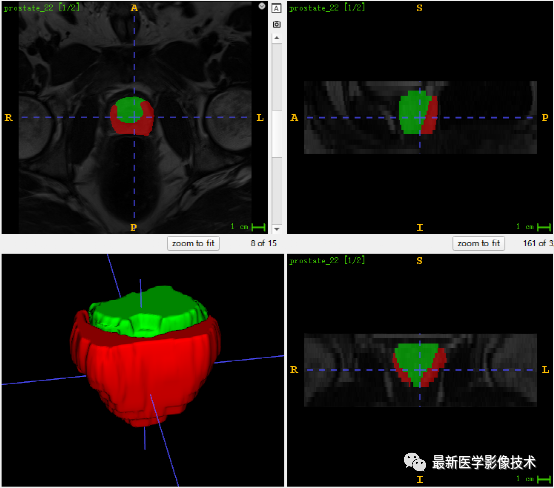

6、测试集分割结果